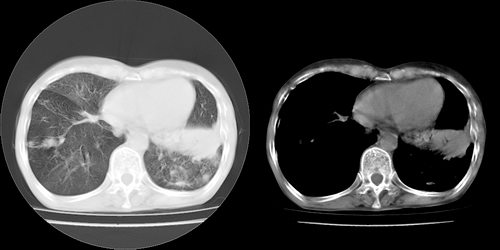

以下是引用lihuuuu在2006-7-18 18:16:00的发言:[br]支持肺结核诊断[br]本病例符合结核“三多”“三少”特征(多病灶、多形态、多钙化、少肿块、少堆积、少增强)中的前五个特征,另外左下叶背段有不张样改变-考虑伴有支气管内膜结核所致段不张。

以下是引用yang4132在2006-7-18 10:04:00的发言:[br]两肺多发 多形态病变,部分半纤维条索和斑点壮钙化,胸膜肥厚粘连,考虑结核。